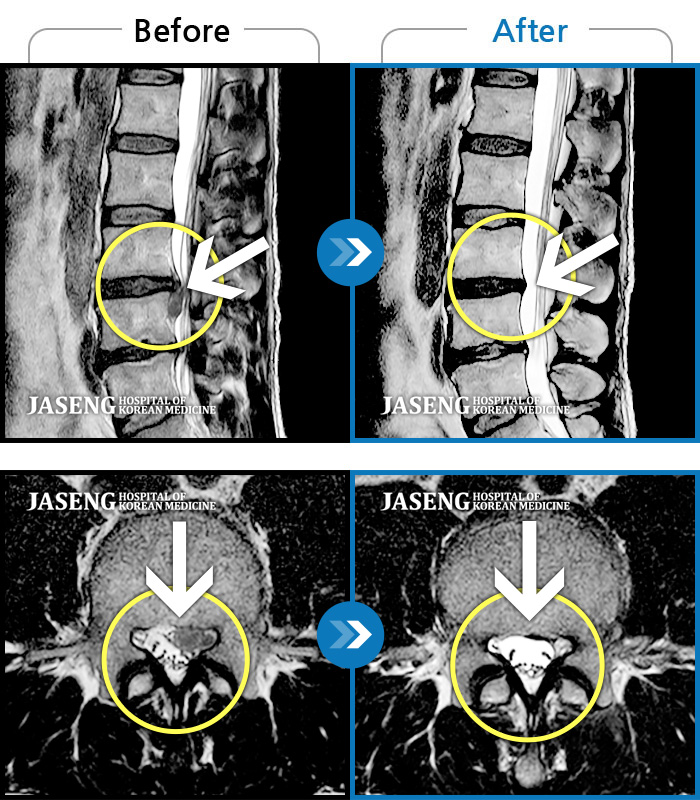

MRI 치료사례

왼쪽 발목과 엄지발가락 힘이 빠지면서 허리 통증